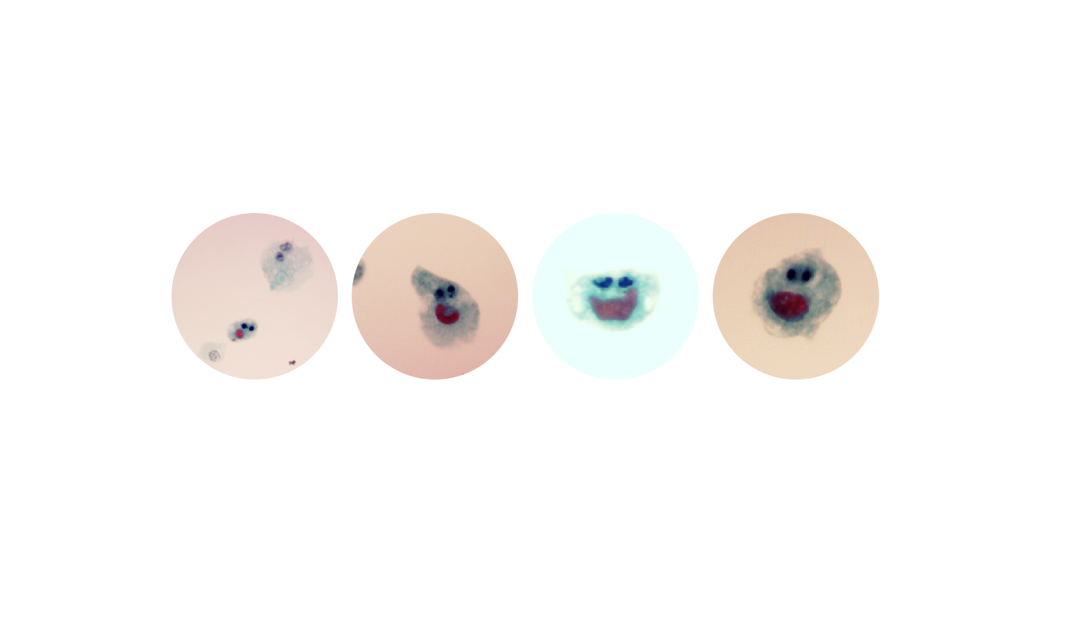

Congratulations to Dr Richard Bishop for the winning entry - Welcome to the urine family - for the month of March 2026.

WINNER Welcome to the urine family Dr Richard Bishop Leeds Teaching Hospital NHS Trust